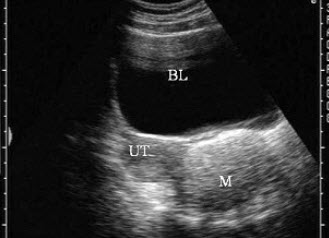

38、单项选择题

女性,出现腰痛并血尿3天,超声检查如图所示,该病例最可能诊断()

如图,女性,26岁,无明显不适,盆腔横断面,最可能的诊断是()

A.炎性包块

B.宫外孕

C.畸胎瘤

D.黄体囊肿

E.正常声像图